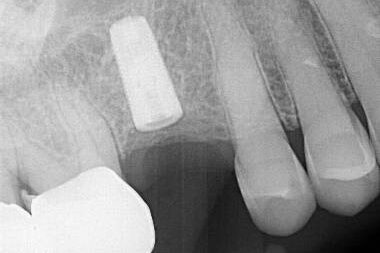

The following Type I case presented with a fractured abutment screw in an Implant Direct Legacy III (blue) implant in the #8 site. This implant had been in function for 9 years. The preoperative radiograph clearly showed the top of the fragment positioned above the top implant thread. There were no previous recovery efforts attempted. As the fragment was mobile with an endodontic explorer, the case qualified as a Type I case. The fragment was rotated out of the implant with the endodontic explorer and recovered. The key to success in this case was understanding the situation prior to recovery and using only the necessary tooling to mobilize an already mobile fragment. Microscopic visualization is always helpful to understand where the lead thread of the fragment is located relative to the implant lead thread.